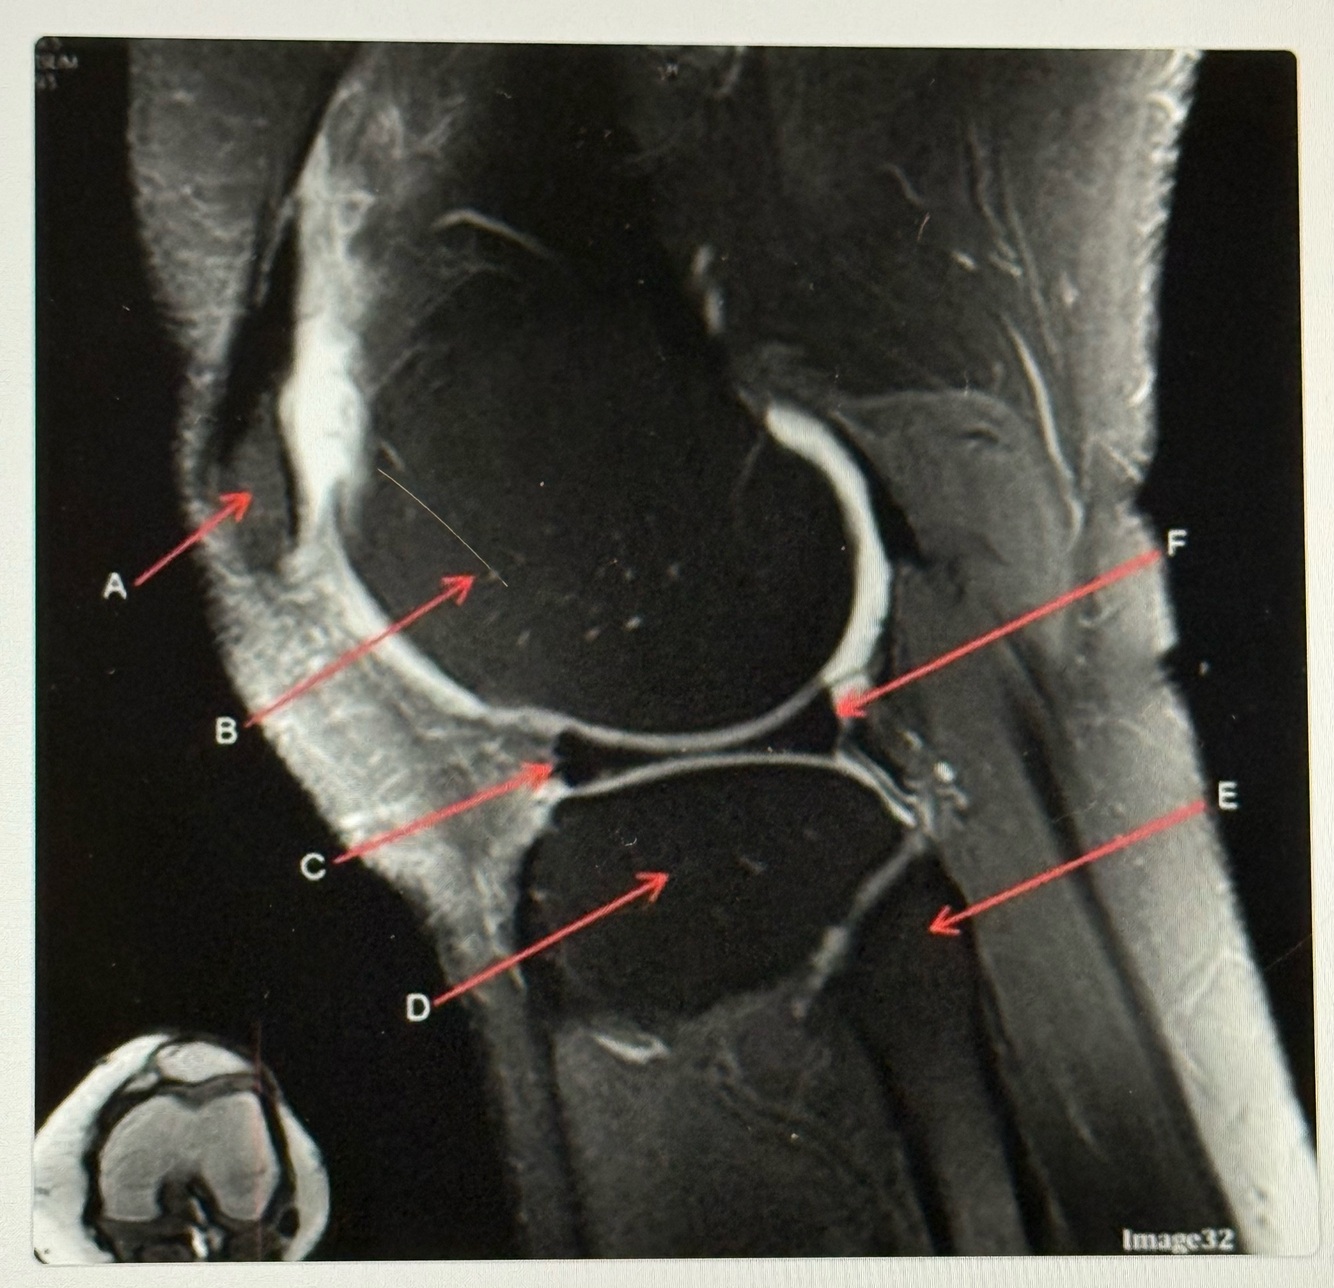

18

Q

Letter E points to the

A

Posterior cruciate ligament (PCL)

How well did you know this?

19

Letter F points to the

Femur

20

Letter D points to the

Lateral femoral condyle

21

Letter C points to the

Medial femoral condyle

22

Letter B points to the

Medial

Collateral ligament (MCL)

23

Letter A points to the